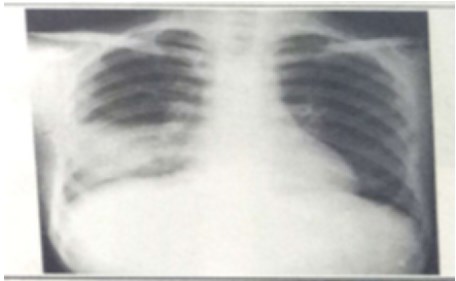

試題:男性,26歲,受涼后寒顫高熱,咳嗽,咳鐵銹色痰5天(2分)

A.肺癌

B.氣胸

C.正常胸片

D.肺炎

答案:D